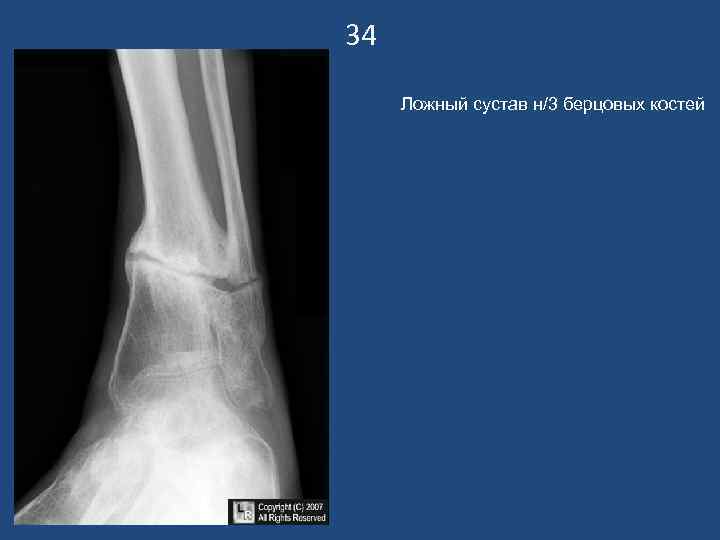

34 Ложный сустав н/3 берцовых костей